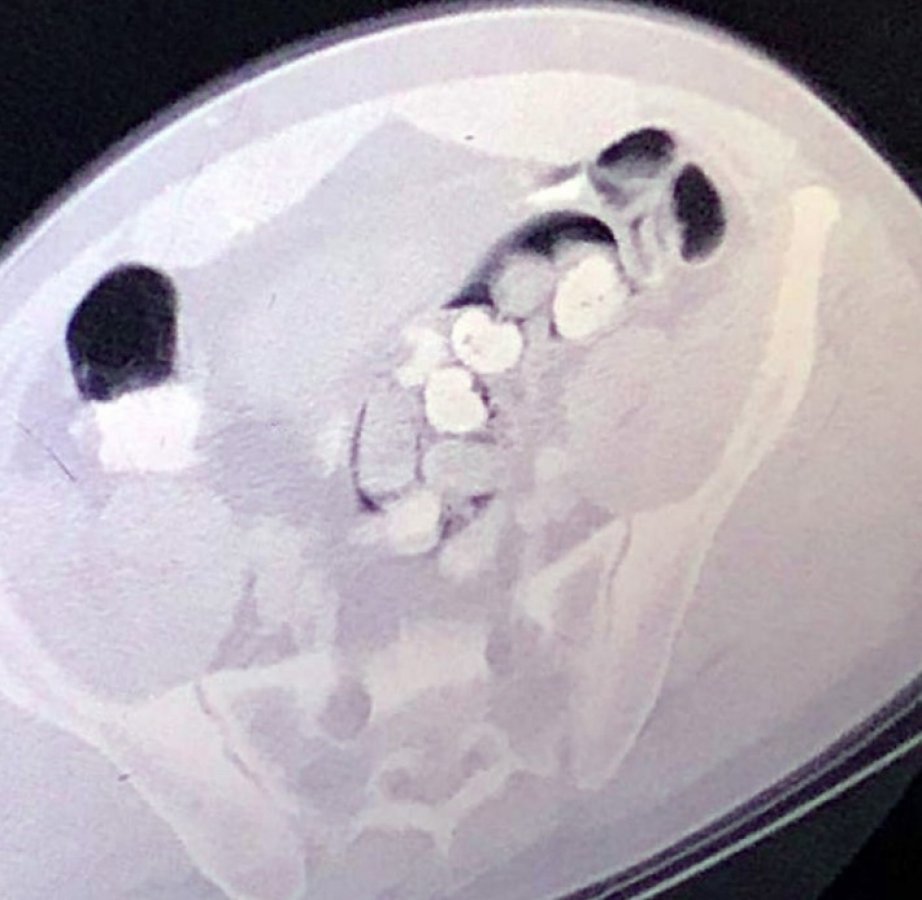

Polis bunun üzerine savcılıktan alınan izinle zanlıyı, Çukurova Üniversitesi Tıp Fakültesi Balcalı Hastanesi Gastroenteroloji Bölümüne götürdü. Burada zanlının bağırsak tomografisi çekildi. Bağırsaklarında serçe parmağı büyüklüğünde yabancı cisimler olduğu tespit edilmesine rağmen zanlı, uyuşturucu olmadığını söylemeye devam etti.